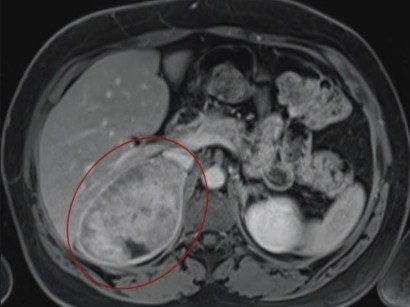

The mri myocarditis protocol encompasses a set of different mri sequences for the cardiac assessment in case of suspected myocardial inflammation. Pdf | on jan 1, 2013, m gutberlet and others published mrt bei myokarditis | find, read and cite all the research you need on researchgate Myocarditis, also known as inflammatory cardiomyopathy, is inflammation of the heart muscle.symptoms can include shortness of breath, chest pain, decreased ability to exercise, and an irregular heartbeat. This article aims to frame a general concept of a cardiac mri protocol in the above setting. Exactly how many people are affected is hard to know because it often has no symptoms.

Stellenwert des late gadolinium enhancement im mrt bei myokarditis february 2021 conference: Thomas alexander ochtrop and dr matt a. Various mri parameters are available which have different accuracies. Myocarditis can affect your heart muscle and your heart's electrical system, reducing your heart's ability to pump and causing rapid or abnormal heart rhythms (arrhythmias). Eine myokarditis kann folge einer nicht ausgeheilten viralen oder sonstigen infektion oder autoimmun, autoentzündlich, toxisch oder allergisch bedingt sein. Myocarditis myocarditis is an inflammation of the heart muscle (myocardium). Heilt in den meisten fällen folgenlos aus, es gibt jedoch auch schwerste verläufe mit komplikationen bis hin zum plötzlichen herztod. 23 january 2013 | der radiologe, vol. Rest and reducing the workload on your heart is an important part of recovery. Explore mayo clinic studies testing new treatments, interventions and tests as a means to prevent, detect, treat or manage this condition. In der mehrzahl der erkrankungen liegt eine virusinfektion mit zerstörung von kardiomyozyten in kombination mit einer. Complications may include heart failure due to dilated cardiomyopathy or cardiac arrest. Myocarditis, also known as inflammatory cardiomyopathy, is inflammation of the heart muscle.symptoms can include shortness of breath, chest pain, decreased ability to exercise, and an irregular heartbeat.

Myokarditis Entlarven Aufgepasst Bei Verschlepptem Infekt Doctors Today from www.doctors.today Prerequisites for this are noninvasive and invasive biomarkers including endomyocardial biopsy and polymerase chain reaction on cardiotropic agents. Myocarditis can affect your heart muscle and your heart's electrical system, reducing your heart's ability to pump and causing rapid or abnormal heart rhythms (arrhythmias). Myocarditis, also known as inflammatory cardiomyopathy, is inflammation of the heart muscle.symptoms can include shortness of breath, chest pain, decreased ability to exercise, and an irregular heartbeat. Cardiac magnetic resonance imaging (cmri) is a versatile diagnostic tool. Myocarditis is inflammation of the heart muscle (myocardium). Thomas alexander ochtrop and dr matt a. Various mri parameters are available which have different accuracies. 23 january 2013 | der radiologe, vol.